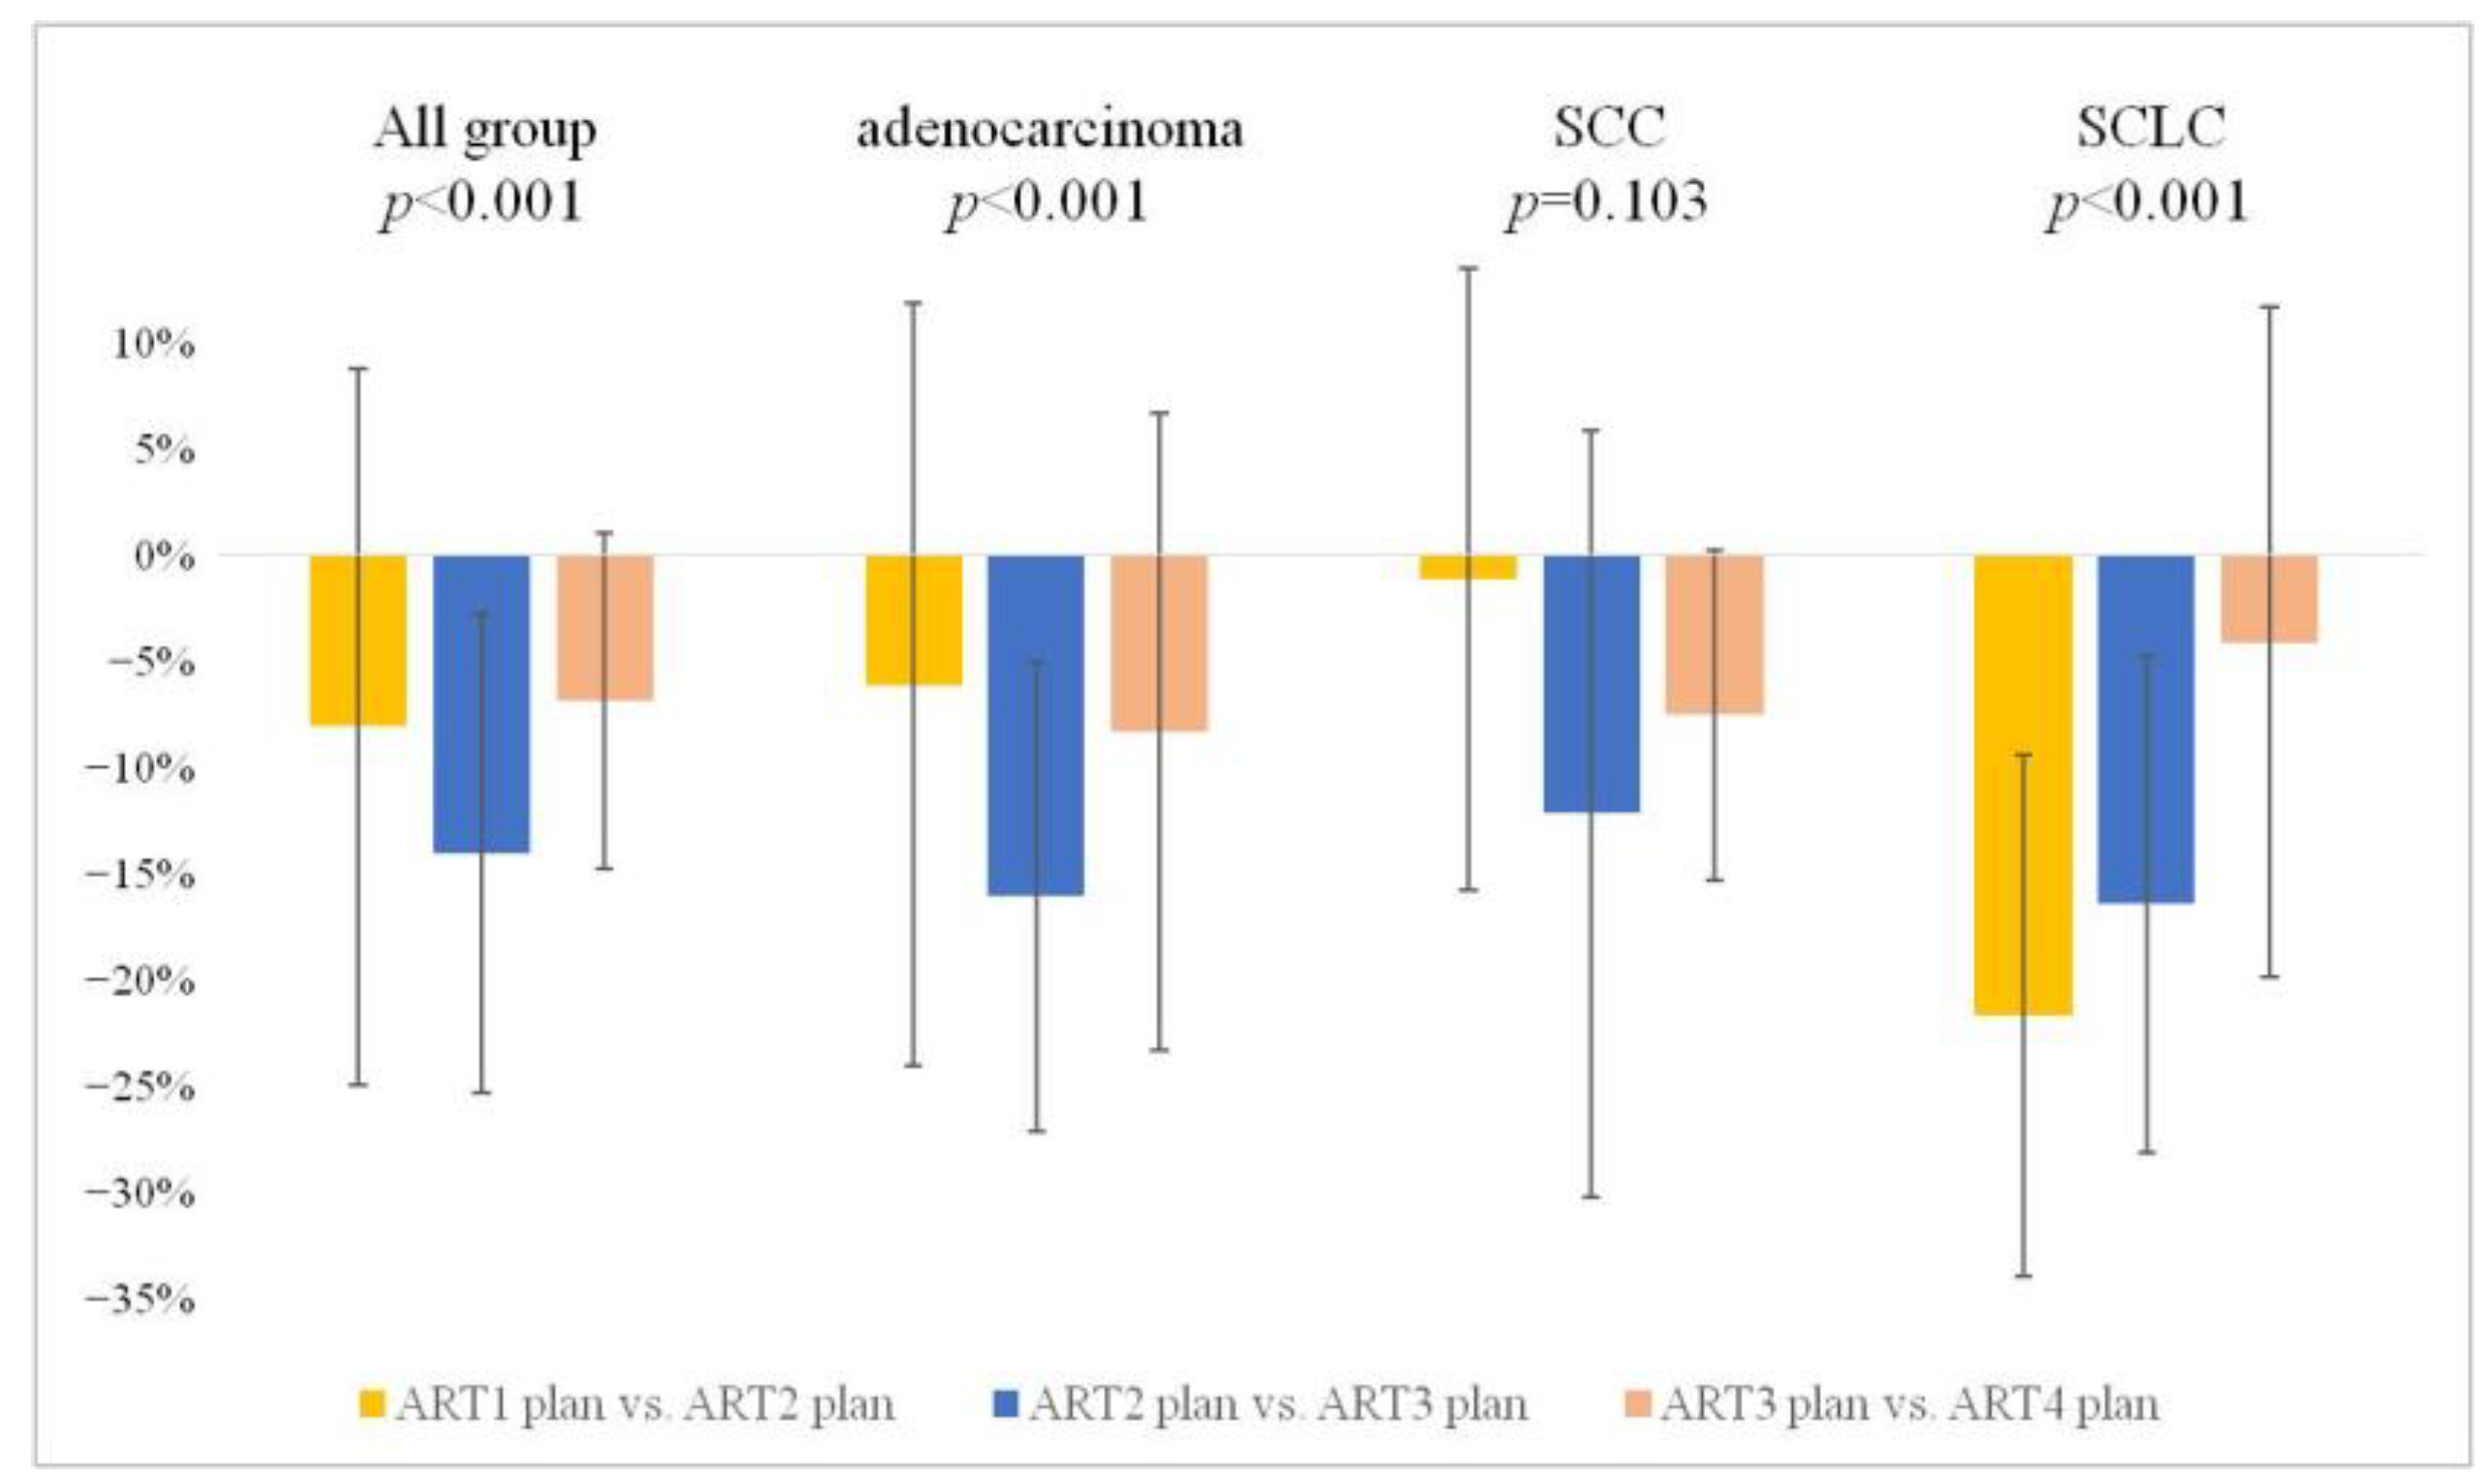

3.3.2. Weekly Interval Comparison of GTV Alterations

| rCT2 GTV rel. (%) | −7.77 ± 16.31 | −5.86 ± 17.39 | −1.07 ± 14.14 | −20.95 ± 11.88 |

| rCT3 GTV rel. (%) | −20.26 ± 19.34 | −20.47 ± 15.11 | −12.68 ± 25.15 | −33.51 ± 14.05 |

| rCT4 GTV rel. (%) | −25.54 ± 19.56 | −26.86 ± 17.53 | −19.03 ± 27.56 | −36.14 ± 13.77 |

| p-value All (abs.) | <0.001 | 0.034 | 0.023 | 0.034 |

| p-value All (rel.) | <0.001 | <0.001 | 0.103 | <0.001 |

| p-value rCT1 vs. rCT2 (rel.) | 0.010 | >0.999 | >0.999 | 0.001 |

| p-value rCT1 vs. rCT3 (rel.) | <0.001 | 0.015 | >0.999 | <0.001 |

| p-value rCT1 vs. rCT4 (rel.) | <0.001 | 0.009 | 0.758 | <0.001 |

| p-value rCT2 vs. rCT3 (rel.) | <0.001 | 0.031 | 0.250 | 0.076 |

| p-value rCT3 vs. rCT4 (rel.) | 0.134 | >0.999 | >0.999 | >0.999 |